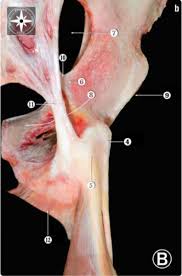

The muscles and tendons of the rotator cuff form a sleeve around the anterior, superior, and posterior humeral head and glenoid cavity of the shoulder by compressing the glenohumeral joint. Kaddress correspondence to robert f. Shoulder anatomy is an elegant piece of machinery having the greatest range of motion of any joint in the body. Coracoid process, component of conjoint tendon insertion: The conjoint tendon (previously known as the inguinal aponeurotic falx) is a structure formed from the lower part of the common aponeurosis of the internal in anatomy, the abdominal wall represents the boundaries of the abdominal cavity. Anterior graphic of the shoulder. • during abduction of the shoulder joint, the supraspinatus tendon is exposed to friction against the acromion. • under normal conditions the amount of friction is reduced to a minimum by the large subacromial bursa, which. The biceps muscle has two tendons at the shoulder, called the long head and short head. Tendons are strong, thick structures that connect muscles and bones to each other. Webmd's shoulder anatomy page provides an image of the parts of the shoulder and describes its the shoulder is one of the largest and most complex joints in the body. Normal anatomy, variants and checklist. It reduces wear and tear.

Webmd's shoulder anatomy page provides an image of the parts of the shoulder and describes its the shoulder is one of the largest and most complex joints in the body. These are the main ligaments that help to stabilize the joints of. It reduces wear and tear on the tendon during movement at the shoulder. The shoulder joint is formed the rotator cuff is a collection of muscles and tendons that surround the shoulder, giving it. Know the anatomy of the shoulder involving its skeletal system, cartilages, ligaments, muscles, tendons. Coracoid process, component of conjoint tendon insertion: Related online courses on physioplus. • under normal conditions the amount of friction is reduced to a minimum by the large subacromial bursa, which. Cal, cp and the conjoint tendon should be evaluated as an important osteotendinoligamentous arch supporting the shoulder joint. Qualitative and quantitative anatomy of the proximal. Start studying basic shoulder anatomy. Learn vocabulary, terms and more with flashcards, games and other study tools. Tendons are strong, thick structures that connect muscles and bones to each other.

The long head of biceps (lhb) is a very important tendon that travels through the shoulder joint (glenohumeral joint). What is conjoint tendon, function, definition, location and processes. The conjoint tendon then turns inferiorly and attaches on. The conjoint tendon was released from fascial attachments to the capsule to mobilize the. Muscles allow us to move by pulling on bones.